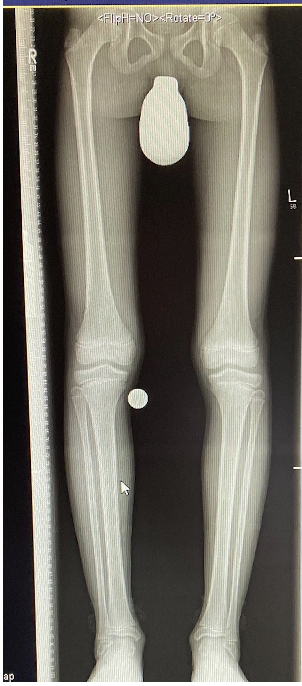

Wachstumslenkung mit moderner Klammer oder eight plate

Bei offenen Wachstumsfugen kann über eine Steuerung des Wachstums mit einer Klammer (Blount-Klammer/Flex Tack) oder kleinen Plättchen (Eight Plate) eine Korrektur von Achsabweichungen in der sagittalen und coronaren Ebene erreicht werden (Abb. 8). Der Hautschnitt beträgt ca. 1,5 - 2 cm und die so versorgten Kinder können ihre Extremität direkt postoperativ schmerzadaptiert voll belasten. Die wachstumslenkende Operation mit einer Klammer oder einem Plättchen besitzt ein enormes Korrekturpotential und erspart dem Kind oder Jugendlichen umfangreiche Umstellungsosteotomien und Plattenosteosynthesen, welche eine Schnittlänge von 15 cm und eine Entlastung des operierten Beines von 4-6 Wochen erforderlich machen.

Abb. 8 a-g: Genua vara prä- und postoperativ versorgt mit Flex Tacks (a-b) und ein Genu valgum versorgt mit Eight Plate an der medialen Femurkondyle (c); Spitzfuß bei congenitalem Klumpfuß und einem Flat Top Talus mit präoperativem Röntgenbild seitlich und der deutlich nach dorsal stehender Tibia(d); intraoperative Bilder der Epiphysiodese mittels Eight Plate zur Wachstumslenkung der distalen Tibia in die Extension (e-f) und postoperativer Verlauf nach sechs Monaten mit regelrecht stehender Tibia über dem Talus durch die distale Extension (g).